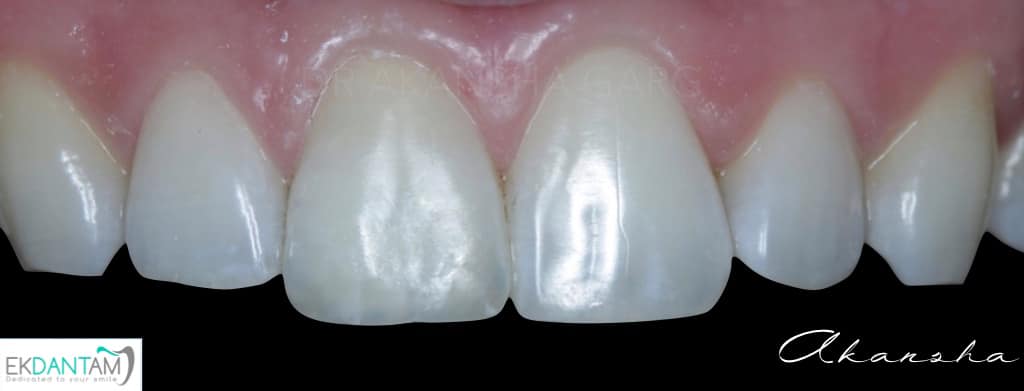

Being gentle to Tooth. It sounds very easy to do subtractive dentistry and grind the tooth and place Crown. The best dentistry is additive dentistry when you save what you have and just replace what’s missing. Case of discoloured tooth due to trauma and Rct years back. Non invasive approach- non vital bleaching followed by composite Incisal edge build up